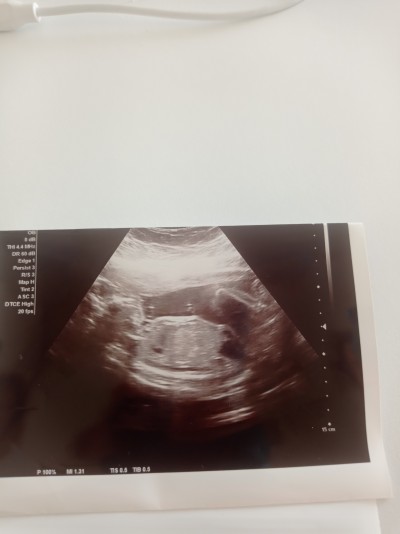

Kafayı yicem Bu pozisyonda cinsiyet görünmez mi arkadaslar

24 haftalık ve doktor asla ilgilenmiyor bir sürü para veriyorum özele 5 dakika bile bakmıyor

Resmen erkek :D

Kordonun altındaki pipi değil mi işte :D

Yok ya o bacakları bence :)

Dizleri kaldırmış gibi duruyor gözükmez ki bacak arasi :)

pipi var bacim orda bebek poz vermis pipim var diye

Ben göremedim ayaklari o bence

Erkek bence:))